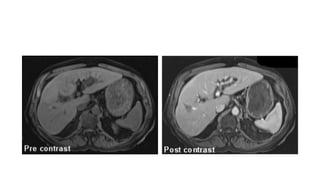

Caso Cerrado 21

Abril Ana Casas

Historia • Varón de 50

años con historia de hepatitis crónica e hipertensión portal